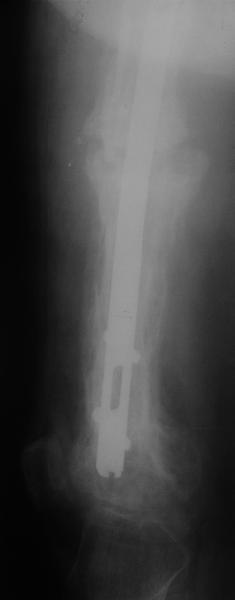

Еще один пример. Пациентка с юга России, прислала рентгенограммы через

год. На сегодня прошло 2 г. 8 мес. после операции. Несмотря на не очень

убедительный процесс сращения, пациентка ходит. Учитывая остеопороз при

Педжете, решили, что динамизировать вообще не нужно.